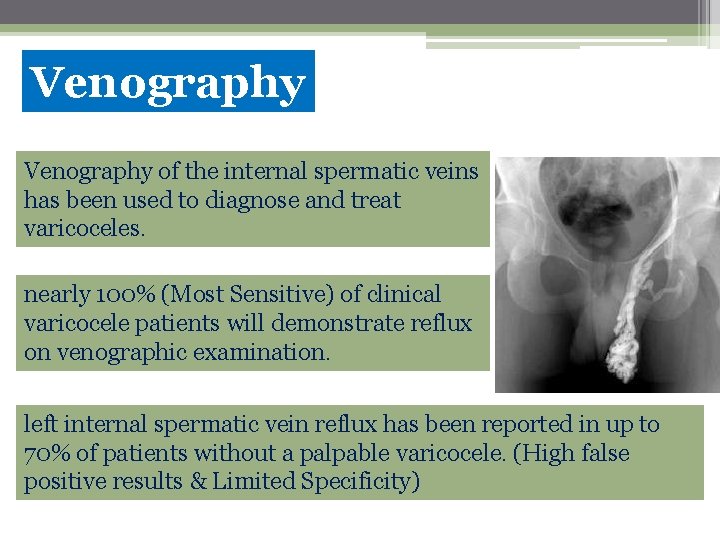

Venography of the internal spermatic veins has been used to diagnose and treat varicoceles. nearly 100% (Most Sensitive) of clinical varicocele patients will demonstrate reflux on venographic examination. left internal spermatic vein reflux has been reported in up to 70% of patients without a palpable varicocele. (High false positive results & Limited Specificity)